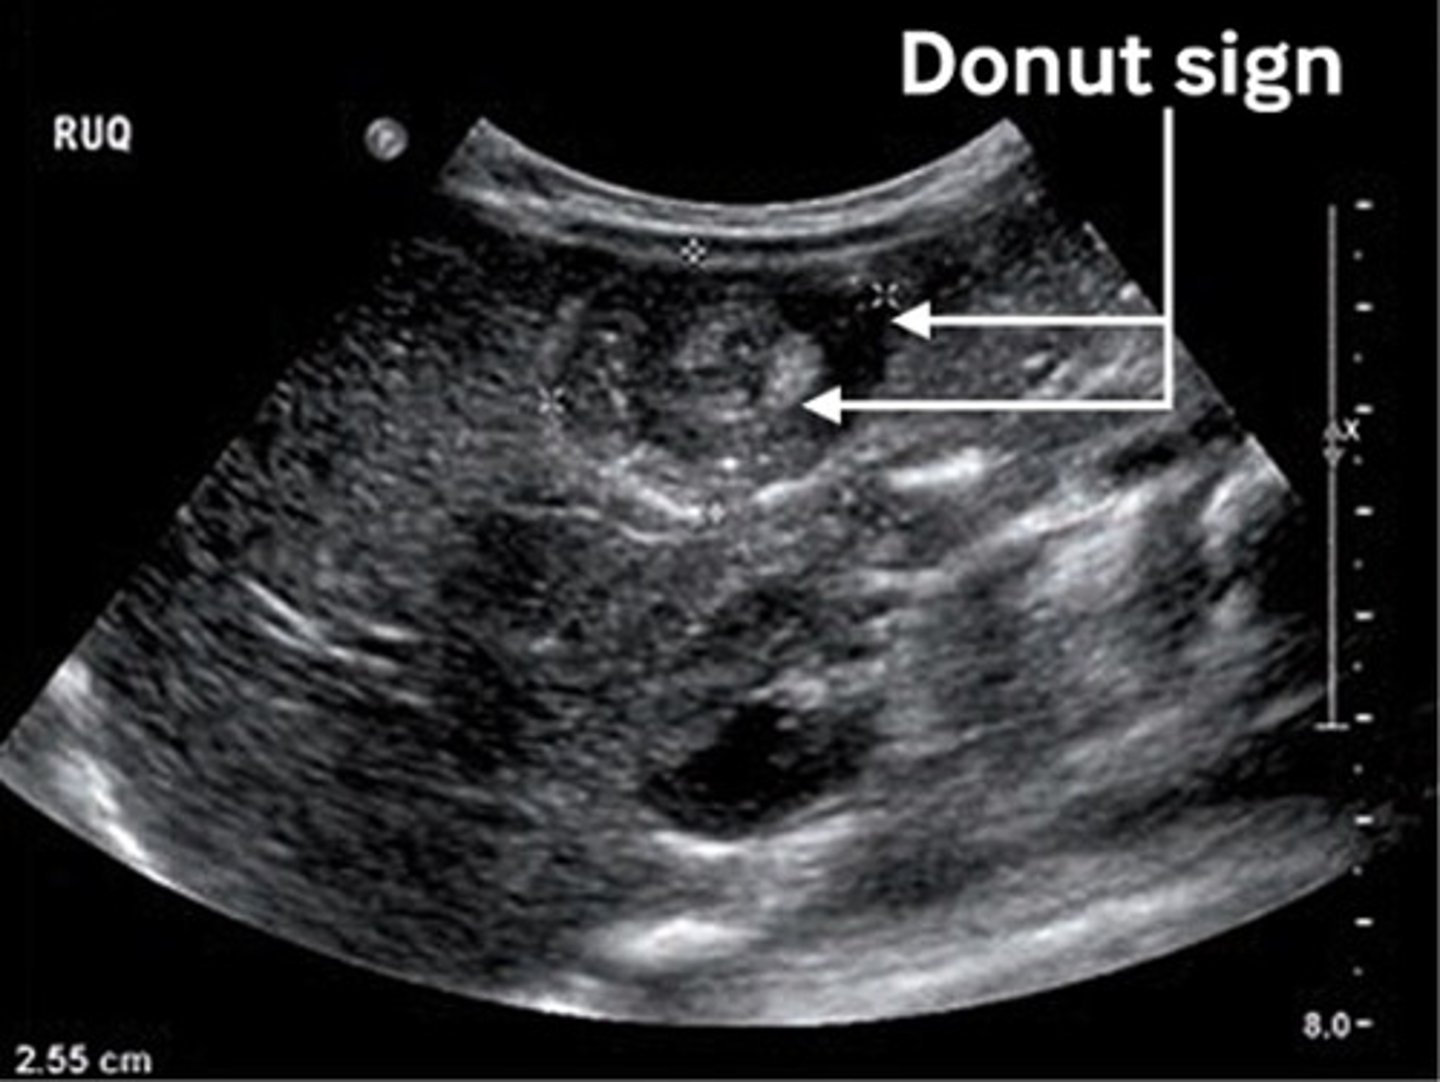

4 mo old patient presents with inconsolable crying and stool containing mucus and blood x 2 days. On PE you palpate a sausage shaped mass in the upper abdomen. What do you expect to see on US?

US: "Target" / "Donut" sign

Tx: Air contrast enema